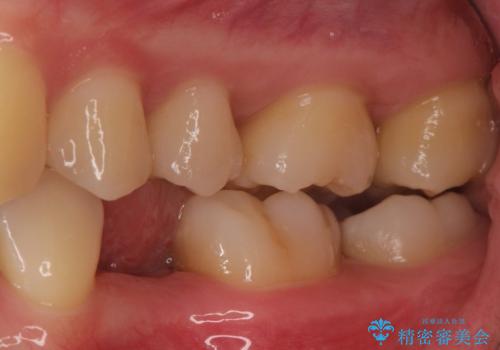

小臼歯のインプラント

- 20代女性

- 6ヶ月

- 小臼歯が先天性欠損していたため、インプラントにて補綴しています。